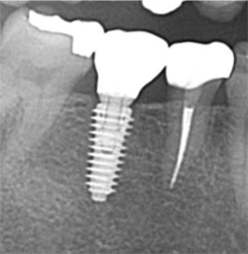

症例4【50代女性】左上6 副鼻腔膜を挙上しインプラント埋入 左上5 歯根破折の為インプラント埋入

治療後(10年経過)

主訴 左上奥歯で物が噛めない。入れ歯は煩わしいので、インプラントを希望。

左上第一大臼歯欠損部位は、骨の高さが3~4㎜しかなく、造骨の為にソケットリフト(骨造成)を行い、骨の高さを確保しインプラントを埋入。

約半年の免荷期間を経て、仮歯を装着、リハビリをし、約7ヶ月後にメタルボンド(金属焼付ポーセレン)を装着。

その後、左上第二小臼歯の歯根破折の為に、2本目のインプラントを埋入。(抜歯即時埋入)

リスクとしては、ソケットリフト(骨造成)による一過性の副鼻腔炎が起きる可能性がある。まれに洞底膜が破れる可能性がある。ただし、膜は約3週で再生するので、膜の回復を待ち、再オペを行う。

費用 111万(オペ。ソケットリフト・人工骨・採血による濃縮血小板生成・仮歯・最終補綴物まで含む)